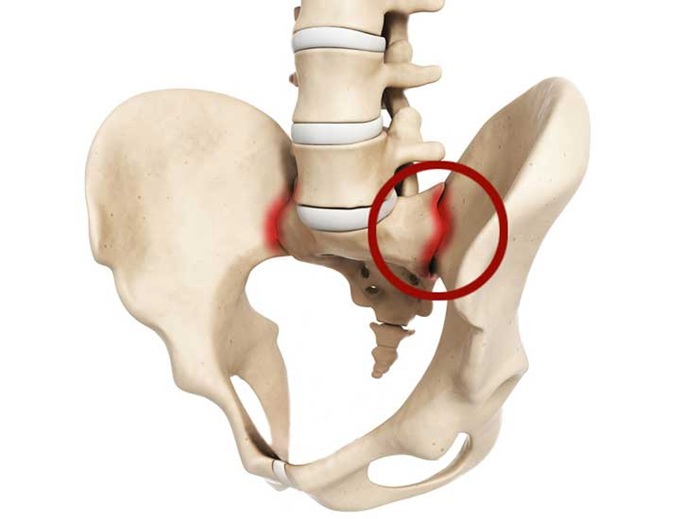

Таз — анатомическая структура, локализованная возле основания скелета. Он образован из двух костей вместе с копчиком и крестцом. Эти детали отвечают за формирование кольца, которое нужно для крепления ног к туловищу. Оно обладает перечнем жизненно важных отделов: репродуктивными органами, лимфоузлами, сосудами, а также мочевым пузырем и участком толстой кишки. Тазовая кость представлена соединением подвздошной, лобковой и седалищной структуры. Вместе они создают вертлужную впадину. Она считается область крепления нижних конечностей.

Соединение крестца вместе с подвздошной костью называют КП-сочленении. Этот сустав считается одним из крупнейших парных сегментов скелета, который удерживается прочными связками. Представленное сочленение взаимодействует с различными мышечными группами:

Заболевание, протекающие в КП-сочленении, вызывает нарушения во всех биомеханических отделах тазового кольца. Аномальная реакция провоцирует изменения прилегающих суставов представленного сегмента, что необратимо приводит к отсутствию возможности двигаться.